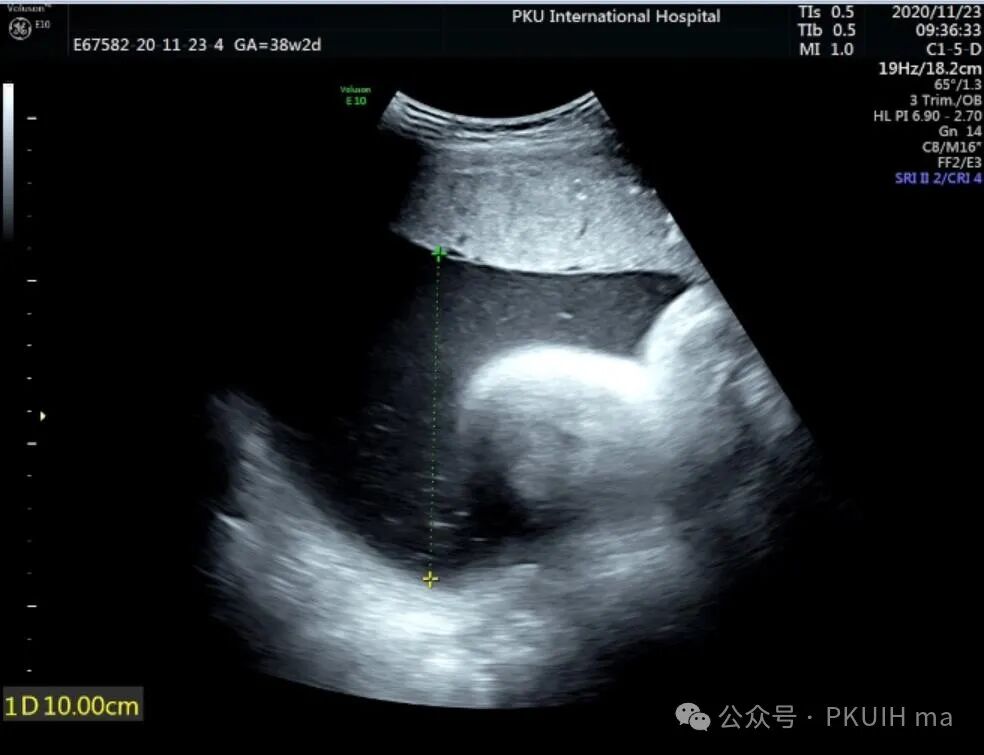

上图是一例在孕晚期发现的肾上腺占位,生后病理证实为神经母细胞瘤的患儿,生后及时做了治疗预后非常好,目前宝宝各项指标都很好。

同时在孕晚期也发现孕妇羊水增多